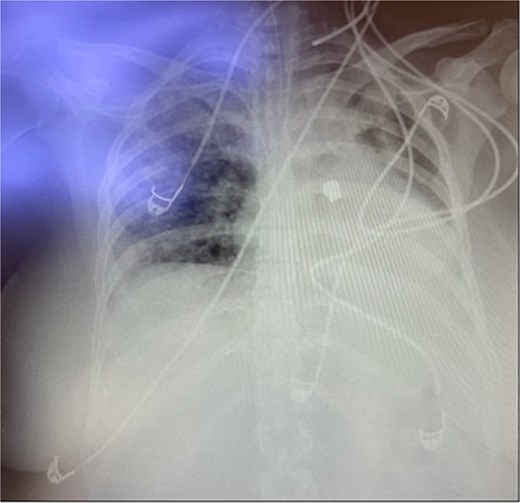

Throughout her 1-month hospitalization, she underwent two extubation trials, both of which were unsuccessful, necessitating reintubation. Extubation trials were unsuccessful due to weak respiratory muscles resulting from prolonged intubation and accumulation of secretions. After the second reintubation, a routine post-intubation chest X-ray incidentally revealed a FB located in the left middle zone of her left lung (Fig. 1). Despite this finding, the patient remained clinically stable with no significant changes in her oxygenation levels or ventilator parameters. The FB was suspected to be a dental bridge, likely aspirated during the second reintubation procedure.

FB aspiration in the tracheobronchial tree is commonly observed in children, with an increasing incidence among adults [4]. Ng et al., 2019, identified cough and recurrent pneumonias as the most common presentations in adults [5]. Diagnosis is typically based on history, physical examination, and radiological investigations, though FB aspiration can occasionally be clinically insignificant. This case highlights a patient who was asymptomatic due to intubation and mechanical ventilation, with the diagnosis made incidentally through a routine ICU chest X-ray. This underscores the importance of imaging in ICU patients, especially those with multiple intubation attempts. However, frequent imaging may not be necessary or cost-effective in all cases, particularly if oxygenation and ventilator parameters remain stable [6].